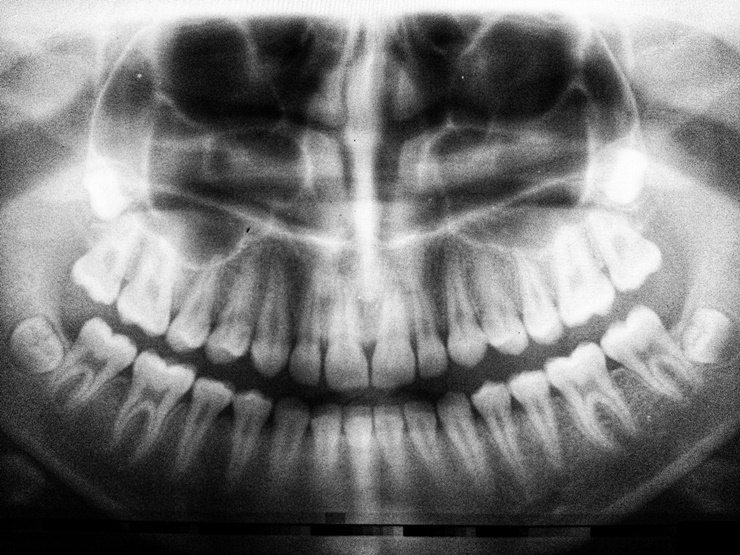

치아 추출 또는 발치를 한 경우에는 치아가 영구적인것이라고 하더라도 사람이 살아가면서 일반적인 절차이다. 주로, 이가 암염 도는 충치, 잇몸 질환, 외상으로 인한 손상, 사랑니 등으로 인해 발치를 시작하게 된다. 발치후 잇몸뼈가 제대로 자라지 않는 경우가 발생할 수 있다. 이 글을 통해, 발치후 잇몸뼈 회복 방법에 대해서 알아보도록 하자.

발치후 잇몸뼈 회복 방법에 대해서 알아봤다. 주로 사랑니 발치 후 잇몸뼈나 치조골에 대해서 관심이 많다. 치조골이 소실되게 되면 결국 임플란트를 할 수 밖에 없다. 부작용으로 발치 후 치열이 나타날 수 있으며, 뼈이식보다는 자신에게 맞는 상황에 따라서 대처하는 것이 가장 옳은 방법이라고 생각된다.